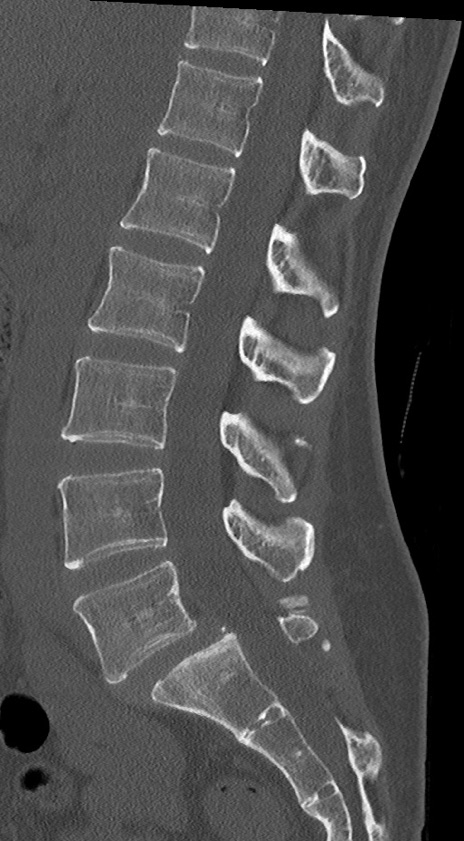

【整形】TIPS症例4 腰椎CT(矢状断像)

腰椎CT

冠状断像